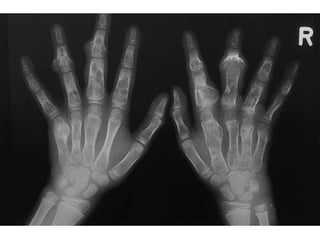

• The commonest location is the tubular bones of the hand,

followed by the femur and humerus.

• Radiographically, the lesion is most commonly central with

rounded, well-defined, lobulated edges and a thin rind of

reactive sclerosis.

• It contains glandular, popcorn, ring-like opacities.

• They can reach considerable size but rarely exceed 6 cm.

• MRI demonstrates the black signal voids of internal

calcification and isotope bone scan is hot in most lesions.

• On X-ray, the chondromas can be very large with

consequent expansion of the bone, thinning of

the cortex or, indeed, no cortex at all (Figure 9.14).

• In Maffucci syndrome, the presence of haemangioma

may be seen on imaging by phleboliths.

• Histologically, the chondromas appear more cellular

than solitary chondromas, with more proliferative

potential.

• Transformation to a secondary sarcoma is seen in both

these conditions.

• In Ollier’s disease, this may occur in 20–30% of

patients; in Maffucci syndrome, this is much more

common and is likely to be greater than 50%.

ENCHONDROMA • This isan intramedullary neoplasm made of well differentiated hyaline cartilage. • The commonest location is the tubular bones of the hand, followed by the femur and humerus. • Radiographically, the lesion is most commonly central with rounded, well-defined, lobulated edges and a thin rind of reactive sclerosis. • It contains glandular, popcorn, ring-like opacities. • They can reach considerable size but rarely exceed 6 cm. • MRI demonstrates the black signal voids of internal calcification and isotope bone scan is hot in most lesions.

MULTIPLE CHONDROMAS AND ASSOCIATEDCONDITIONS • In Ollier’s disease, multiple chondromas may be found within the hand of one limb, or have a much wider, hemisomic distribution, or affect the entire body with a hemisomic prevalence. • The disease is non-hereditary and sporadic. • It most commonly affects the tubular bones of the hand or foot. • Chondromas normally present as bony swellings in childhood which may cause deformities and limb length discrepancy due to epiphyseal fusion anomalies.

• 39.

• In Maffuccisyndrome, multiple chondromas are associated with multiple cutaneous or deep haemangiomas. • On X-ray, the chondromas can be very large with consequent expansion of the bone, thinning of the cortex or, indeed, no cortex at all (Figure 9.14). • In Maffucci syndrome, the presence of haemangioma may be seen on imaging by phleboliths. • Histologically, the chondromas appear more cellular than solitary chondromas, with more proliferative potential. • Transformation to a secondary sarcoma is seen in both these conditions. • In Ollier’s disease, this may occur in 20–30% of patients; in Maffucci syndrome, this is much more common and is likely to be greater than 50%.